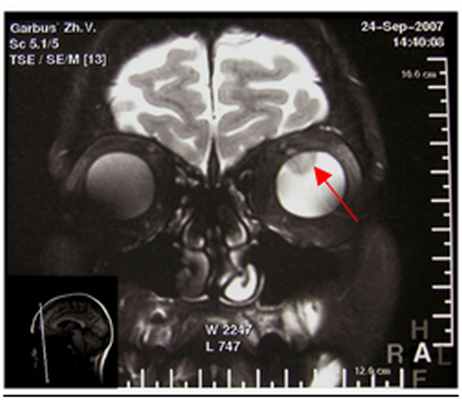

6. КТ\МРТ орбит – бесконтактный метод диагностики, позволяющий в ряде случаев выявить внутриглазное образование, вторичную отслойку сетчатки.

Горшков И.М. представил результаты комбинированной схемы лечения пациентов с меланомой хориоидеи после эндорезекции опухоли, предложив собственный подход. Эндорезекция в ряде случаев может быть альтернативой энуклеации при лечении «больших» меланом хориоидеи (Рис.3). Несмотря на то, что данный способ лечения предполагает, как правило, повторные хирургические вмешательства, несомненным его преимуществом является реальная возможность сохранения глаза и зрительных функций.

О возможностях и первых результатах применения стереотаксической радиохирургии «Гамма-нож» при лечении пациентов с меланомой сосудистой оболочки большого размера рассказала Голубева О.В. (рис. 7).

Исходя из литературных данных, показатели выживаемости и метастазирования сопоставимы с результатами после традиционных органосохраняющих методов лечения и энуклеации. Все пролеченные пациенты находятся под наблюдением, по результатам общего обследования признаков дессеминации процесса не выявлено.

По предварительным данным, стереотаксическая радиохирургия с помощью Гамма-ножа позволяет провести органосохраняющее лечение у пациентов с большими увеальными меланомами, при этом удается сохранить зрительные функции. Развившиеся радиоиндуцированные осложнения выражены умеренно. Необходимо дальнейшее изучение метода для объективной оценки его возможностей и определения места в системе органосохраняющего лечения пациентов с меланомой хориодеи.